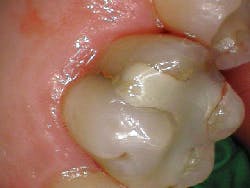

A radiograph assessment revealed a slight radiolucency at the apex of the palatal root on tooth No. 3 (figure 8). Biting and percussion was WNL; probing depths were 6 mm interproximal and 3–4 mm on the facial/lingual. Cold and electric pulp tests were negative. The vestibular area in the No. 3–4 area was tender to palpation. Clinically, a large fracture line was noted on the lingual and on the distal marginal ridge (figure 9).

Diagnosis: Necrotic No. 3 with likely association of extended fracture line into the pulpal space. Recommendations were given to the patient, who opted for extraction and eventual implant placement. Upon removal of the tooth, the following was noted (figure 10):

- Lingual fracture line extending approximately 5 mm below the CEJ

- Existing restoration was removed and the crack line was observed to run across the pulpal floor in a mesiodistal fashion

- Wedging was done, and there was a noted flexuration in the cusps